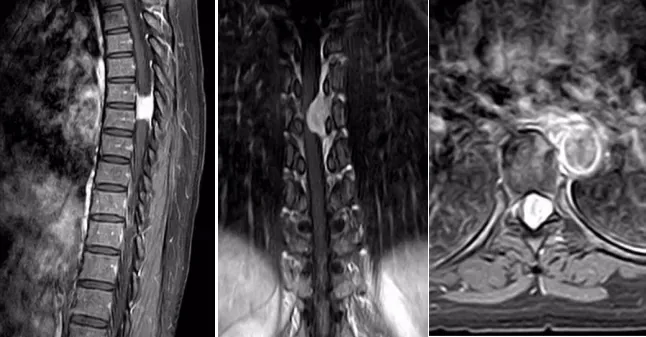

一位女性患者,11个月前没有明显诱因出现双下肢麻木、无力症状,同时伴有排便无力和间歇性跛行的情况,当时并未引起重视。一段时间后,病情逐渐加重,10天前竟严重到无法行走。为寻求治疗,患者来到我院脑外科就诊。门诊通过胸椎 MRI+增强检查发现,胸6-7椎管内左缘髓外硬膜下富血供肿瘤,再结合CT检查后,考虑脊膜瘤,于是以“椎管内占位性病变”将患者收入脑外科住院治疗。

入院后,脑外科团队积极开展术前准备工作。经过详细诊断,基本确定为椎管内肿瘤,脊膜瘤的可能性最大,决定为患者实施肿瘤切除术。术中可见肿瘤呈砂砾状,大小约1.5×2.2cm,颜色呈灰白色,血供丰富且质地坚韧,相应位置的硬脊膜增厚,脊髓受压明显且向右移位,不过幸运的是,肿瘤与脊髓并无明显粘连。在显微镜下,医护人员小心翼翼地将肿瘤分离,严密保护脊髓,最终分块将肿瘤完全切除,病理诊断结果为脊膜瘤。患者恢复良好,现已顺利出院。